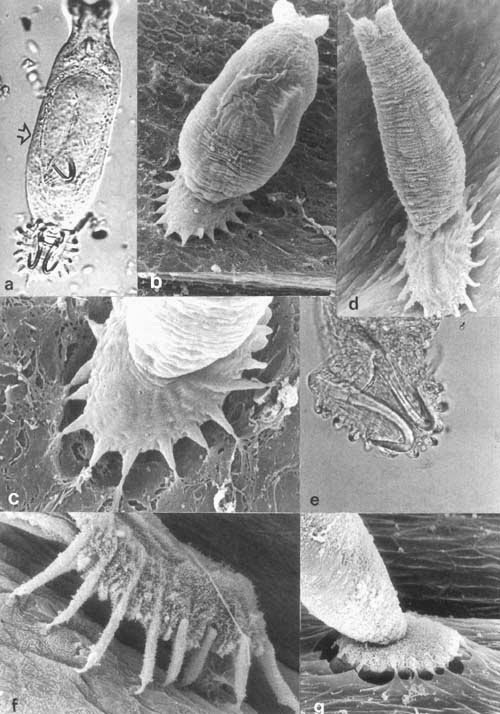

The upper image shows the PNEC’s in your respiratory tract (NE). They can be alone or be grouped into neuro- endocrine bodies (NEBs). A 2008 study, and several before it, has correlated a hyperplasia and hypertrophy of PNECs with Sudden Infant Death Syndrome. Too many and your respiratory control may get thrown out of whack; it may just stop working. It might be good to monitor the PNEC system in youngsters to try and predict susceptibility to SIDS. |

For one example, there are pulmonary neuroendocrine cells (PNEC) in every part of your respiratory tract, from your nose to your alveoli. While they seem to act like neurons in many respects, they are derived from epithelial tissue, not the neural crest tissue that all neurons come from.

Each PNEC spans the distance from basement membrane to the air conducting space. On the luminal side, they have microvilli that stick out into the lumen and sample the air as it passes. On the basal side (bottom) they communicate with neurons. Just what are they doing there?

They have several functions, including regulating the development of the respiratory system in the fetus. They also regulate the function of the respiratory cells by sensing oxygen levels, controlling the muscular tone of the bronchi, regulating pulmonary blood flow and modulating immune responses. The origin and function of PNEC’s is reviewed in a 2012 paper, which also highlights a problem with them – when PNEC’s go bad, they cause a deadly small cell cancer.

In response to what the cell senses, it will release a variety of chemicals, many of which can act as neurotransmitters – hence the reason they are considered neuroendocrine cells. But the PNEC’s may have another function, one hinted at in a 2014 study. The results of these experiments indicated that PNEC’s can detect chemicals in the air as it passes over their microvilli – they quite literally can smell the air, as their microvilli were found to have olfactory (smell) receptors, just like in your nose!